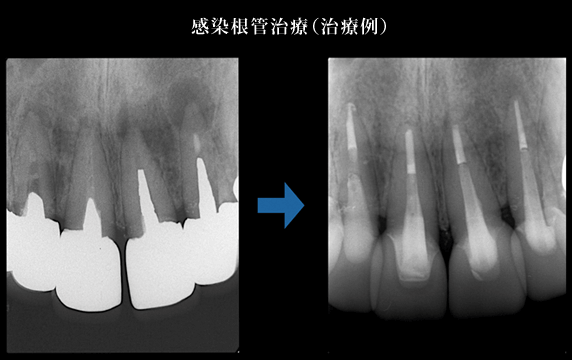

5.経過観察後の治癒の確認

治療後の症状の変化をレントゲンで確認します。

歯の根の中にある神経や血管は、虫歯の進行によって細菌感染してしまいます。また、神経がない歯も細菌感染していれば痛みや腫れといった症状があらわれます。このような場合に歯の根の中を消毒し、細菌の再侵入を防ぐ治療を「根管治療」といいます。